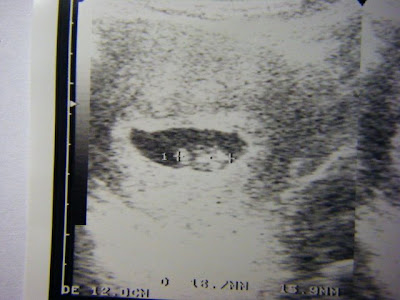

尾巴再見

這是八週多時照的超音波照,此時已經逐漸要跟在一起兩個月的尾巴說再見囉!!